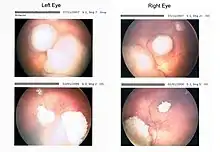

Drawing of a large retinoblastoma

Funduscopic finding of a retinoblastoma

Ocular fundus aspect of retinoblastoma

Large exophytic white tumor with foci of calcification producing total exudative retinal detachment